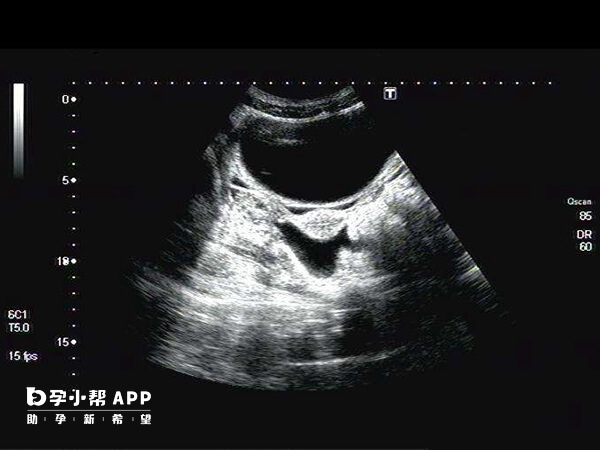

幼稚子宫结构和形状大致正常,但是体积比正常子宫小,而且宫颈相对较长。同时,宫颈外口小,颈管呈圆锥形。幼稚子宫的症状体现在少女月经初潮延迟或者月经稀少,有痛经,甚至闭经。

正常情况下,女性发育成熟后,子宫具备了生育能力。但如果脑垂体,下丘脑,卵巢发生了异常,使内分泌功能出现障碍,子宫发育迟缓,就可能出现幼稚子宫。